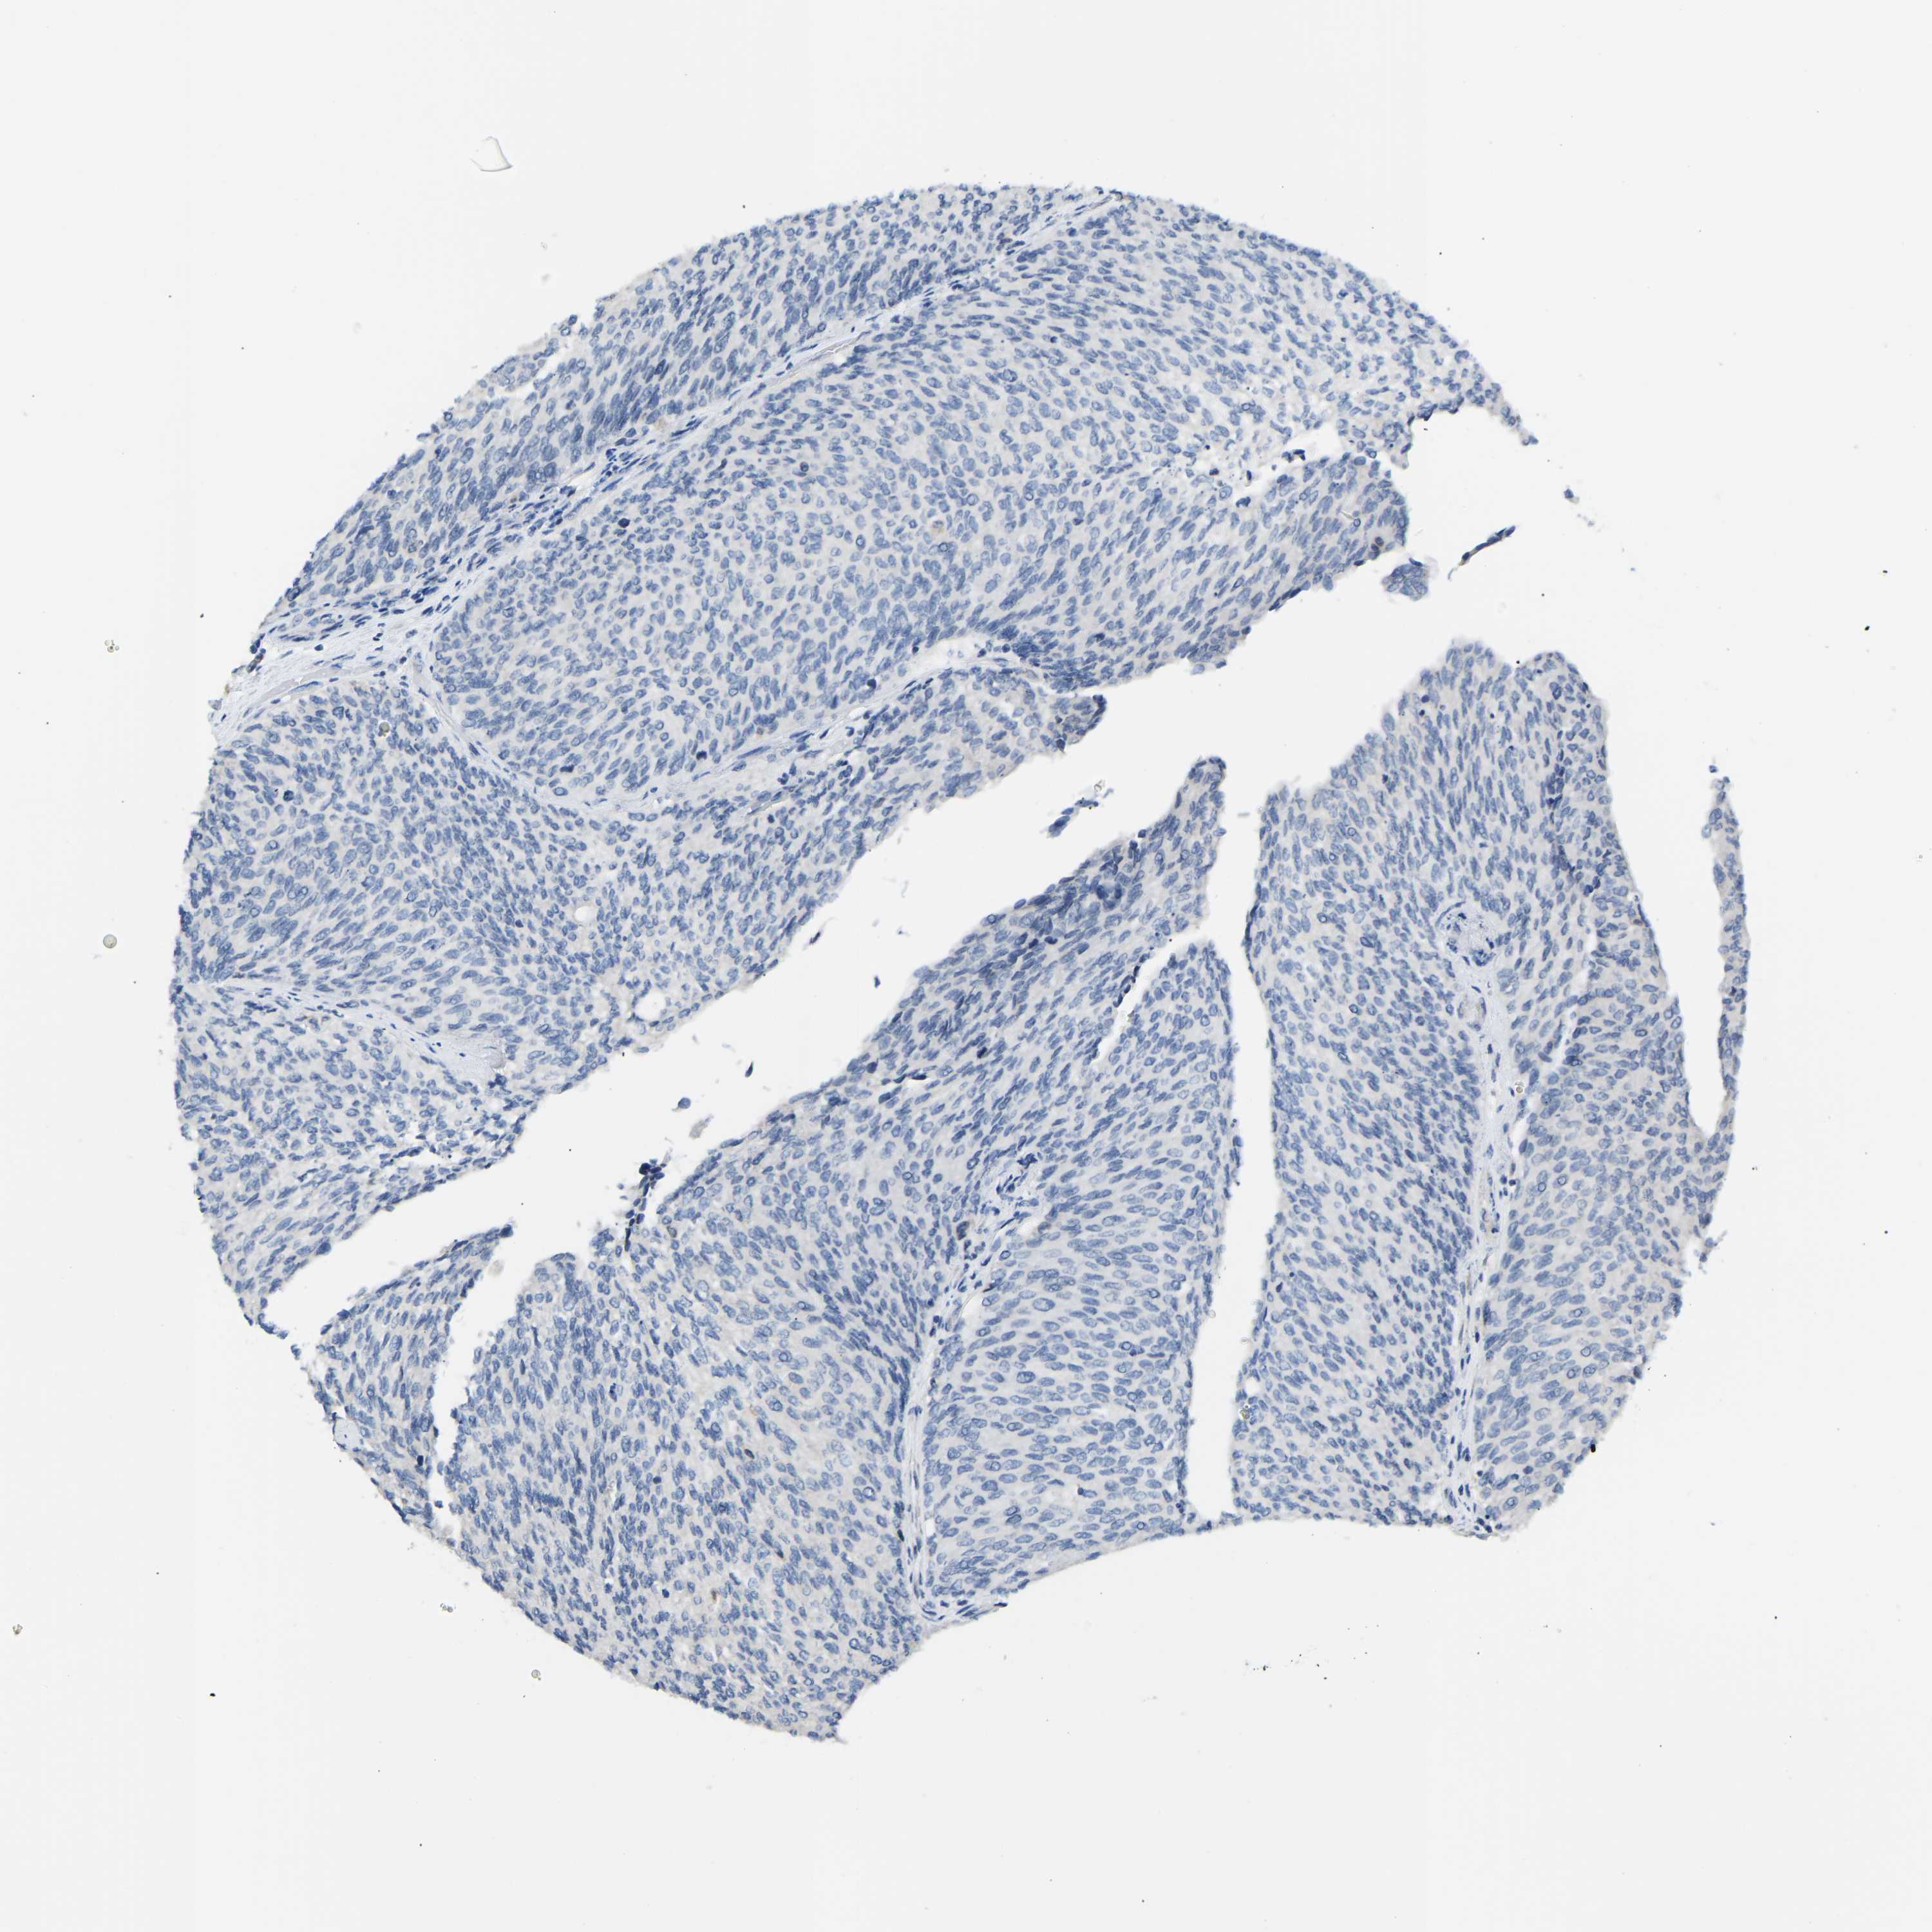

UROTHELIAL CANCER - Protein expressioni

A mouse-over function shows sample information and annotation data. Click on an image to view it in a full screen mode. Samples can be filtered based on level of antibody staining by selecting one or several of the following categories: high, medium, low and not detected. The assay and annotation is described here.

Antibody stainingi

Antibody staining in the annotated cell types in the current human tissue is reported as not detected, low, medium, or high, based on conventional immunohistochemistry profiling in selected tissues. This score is based on the combination of the staining intensity and fraction of stained cells.

Each image is clickable and will lead to virtual microscopy that enables deeper exploration of all samples and also displays staining intensity scores, fraction scores and subcellular localization as well as patient and tissue information for each sample.

Antibody HPA000660

Antibody HPA017929

Staining

High

Medium

Low

Not detected

Intensity

Strong

Moderate

Weak

Negative

Quantity

>75%

75%-25%

<25%

None

Location

Nuclear

Cytoplasmic/membranous

Cytoplasmic/membranous,nuclear

Urothelial carcinoma, High grade

Urothelial carcinoma, Low grade